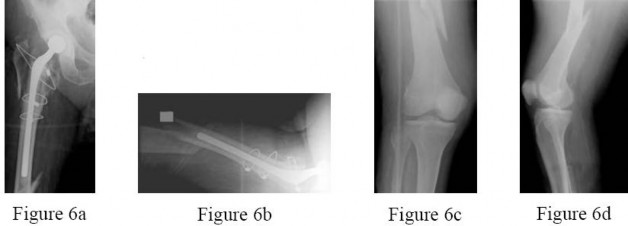

A 70-year-old man underwent removal of an infected total hip arthroplasty (THA) and insertion of an articulating antibiotic-loaded spacer to treat a deep periprosthetic hip infection. He was in a nursing home receiving intravenous antibiotics 3 weeks after surgery when he tripped and fell. Examination shows swelling in the mid and distal thigh, intact skin and neurovascular structures, and severe pain with knee or hip movement. Radiographs of the

femur are shown in Figures 6a through 6d. What is the most appropriate treatment for the fracture below the implant?

Explanation

This patient has a type C periprosthetic femoral fracture. The articulating spacer is not involved in the fracture, which is well distal to the implant. The most appropriate treatment is open reduction and internal fixation of the fracture. Traction is not appropriate for this fracture because it can be treated surgically despite the history of previous hip infection. Traction would also be needed for at least 5 weeks to delay surgical treatment of the periprosthetic fracture until the time of second-stage revision THA. The fracture is fairly distal and revision to a longer antibiotic-loaded implant or uncemented stem is not suitable for this fracture pattern because it extends well past the isthmus. A femoral stem in the distal fragment would provide little stability for the fracture. Additionally, removing the articulating spacer and reimplantation using a long-stem fluted uncemented hip replacement is not appropriate because it would be premature to reimplant this man’s hip while he is still receiving treatment for his deep-hip infection. PREFERRED RESPONSE: 2